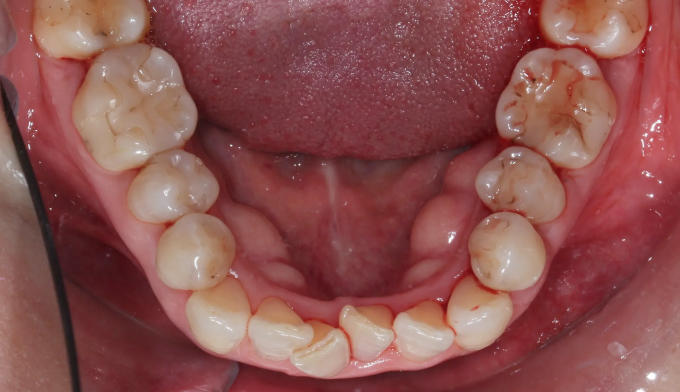

덧니

교정치료에 나이 제한은 없습니다.

건강한 잇몸을 가지고 있다면 60,70대에도 전혀 문제없고, 잇몸이 건강하지 못하다면 20대여도 교정이 힘들 수 있습니다.

아무래도 나이가 있으면 세포활성이 떨어지고 피부의 탄력도 줄어들기 마련입니다.

따라서 섣불리 발치교정을 진행하여서는 안됩니다. 오히려 교정후에 더 나이들어 보이는 경우가 생길 수 있기 때문입니다.

비발치교정을 통하여 치아를 배열하고 일부러 앞니를 조금 더 앞으로 이동시켜 깊어진 팔자주름을 옅게 만들어주었습니다.